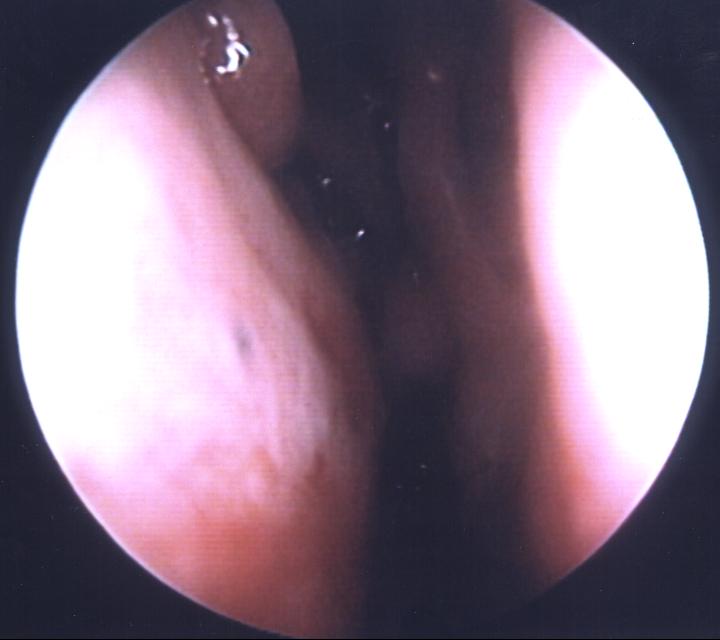

The patient on the right has had a partial left middle turbinate resection, and a graft to the septum bulks up the area to simulate a middle turb.  This patient was perhaps 50% better after an initial surgery - further augmentation has provided further benefit.